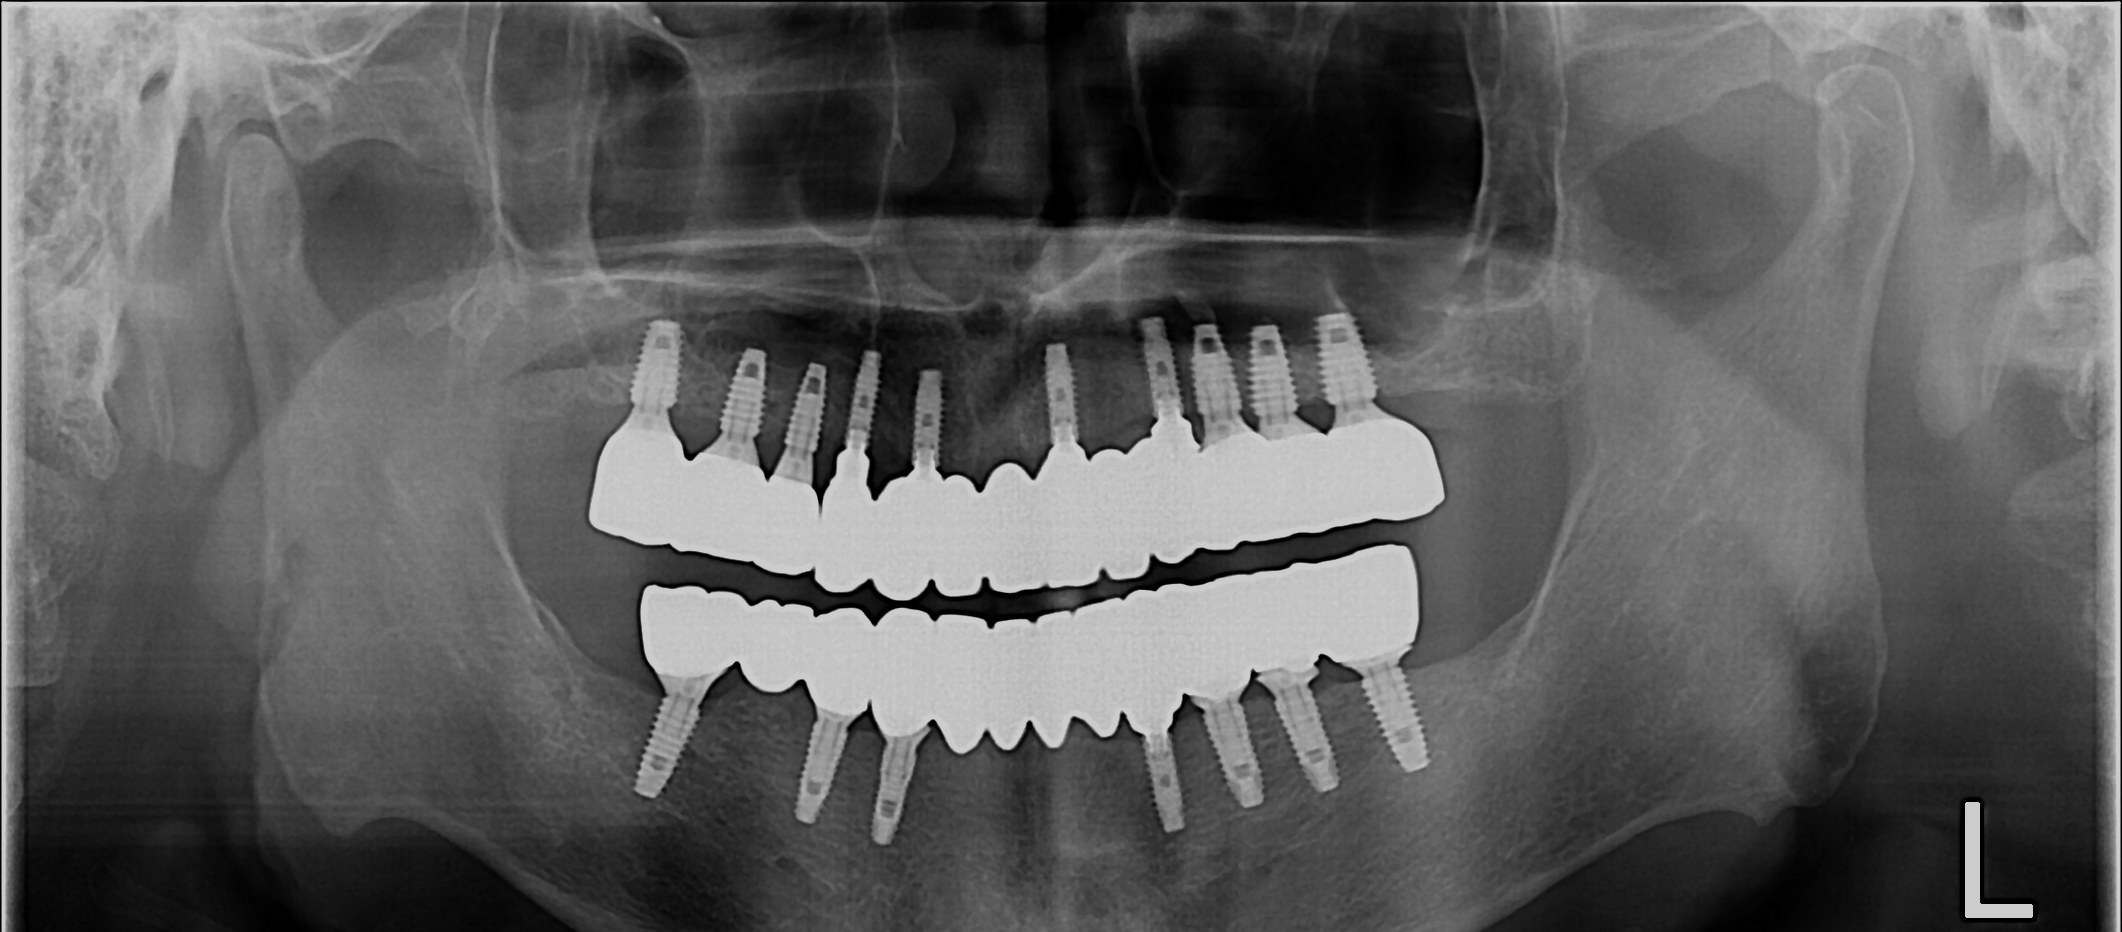

After

무치악 임플란트 회복 Full Mouth Rehabilitation